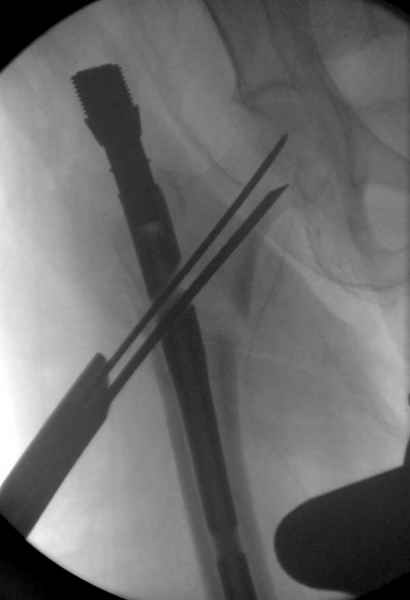

Мы получили испытательный вариант инструментария для пробы, хотя компания объявила, но ещё не для широкой публики, обещают к сентябрю. За полтора месяца, включая сегодняшнюю, вот уже восьмая операция по счету. Удобный инструментарий, ничего лишнего, научились делать быстро, посмотрим что будет, пока нравится.

Здесь сканнированные снимки импланта и операционные снимки больной.

На этом снимке процесс компрессии нижним болтом.